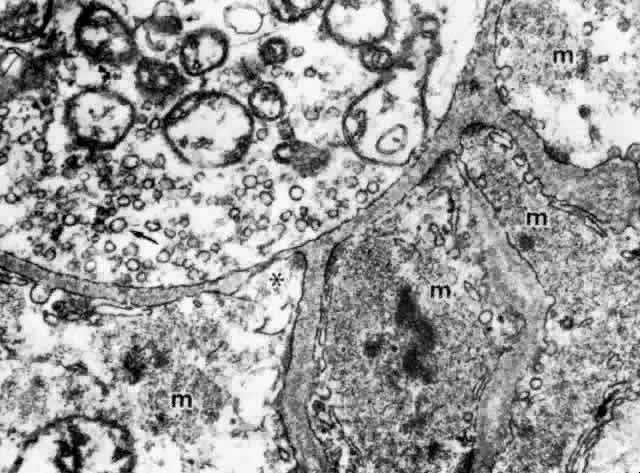

The ciliary muscle is richly innervated with large numbers of cholinergic

nerve terminals. These show primarily the small agranular vesicles

characteristic of cholinergic neuromuscular junctions51 (Fig. 39), consistent with the virtually complete inhibition of ciliary muscle

contraction resulting from use of atropine. Most investigators have described

three types of neuromuscular junctions in the ciliary muscle.46–48,51–53 The most common synaptic junction has an indirect muscle cell contact, with

basement membrane intervening; direct contacts are less frequent (see Fig. 39).  Fig. 39. Dense and lighter muscle fibers (m) around an unmyelinated nerve fiber

one (asterisk) site of direct cell-to-cell contact are seen. (X 53,000) Fig. 39. Dense and lighter muscle fibers (m) around an unmyelinated nerve fiber

terminal that contains many mitochondria and small agranular synaptic

vesicles (arrow), indicating that this is aneuromuscular parasympathetic

junction. Indirect contacts with intervening basement membrane and

one (asterisk) site of direct cell-to-cell contact are seen. (X 53,000)